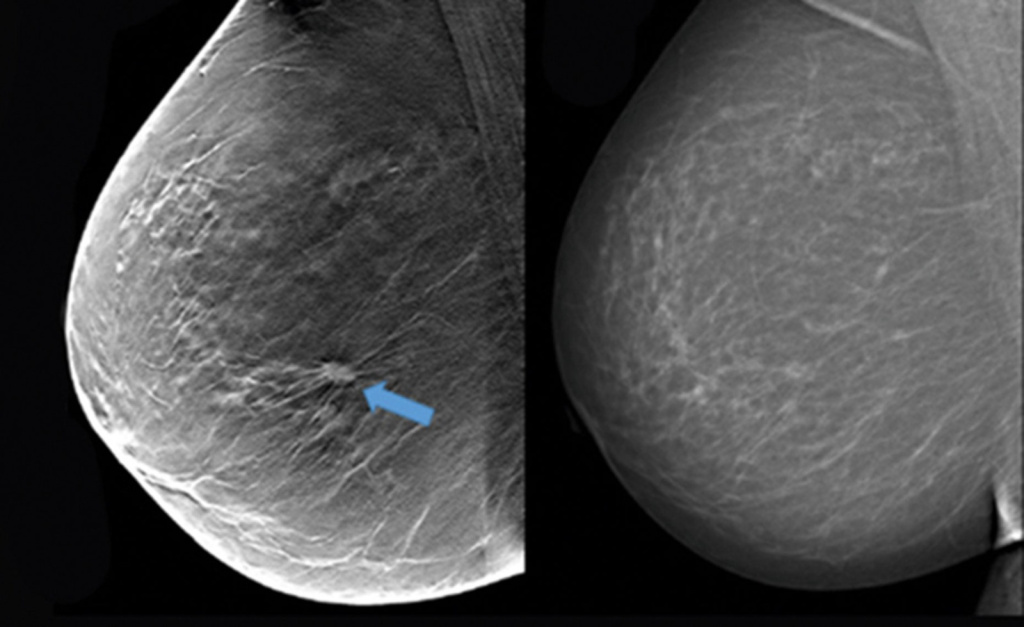

Женщины знают, что в течение жизни необходимо следить за состоянием своей груди, проводя самообследование и посещая врача, чтобы вовремя обнаружить проблемы, требующие лечения. Одним из исследований, необходимых для проверки тканей груди, является маммография.

Ростовчан и гостей города клиника «ДонМед» приглашает на обследование, которое проводят на современном оборудовании экспертного класса. Его выполняет специалист с большим опытом работы, который может обнаружить даже незначительную патологию.